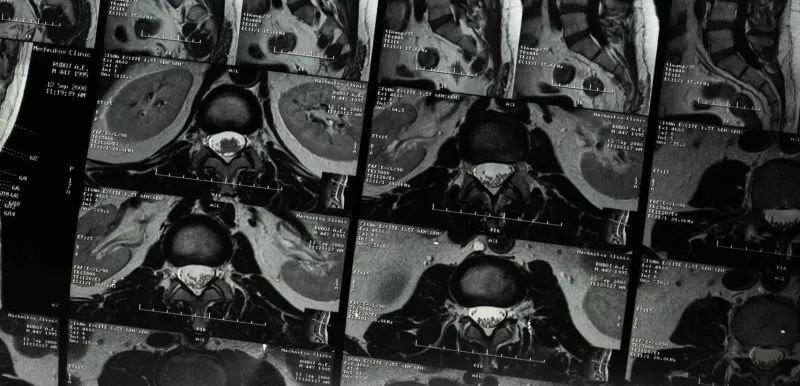

Facts about prostate cancer that spread to bones March 19, 2021 Prostate cancer is one of the types of cancer that is most likely to spread, or metastasize, to bones. There are four main stages of prostate cancer, and stage 4 often involves bone metastases.Bone metastases occur in more than 60 percent of those with advanced prostate cancer. Although prostate cancer that spreads to the bones can’t be cured, you can take steps to strengthen weakened bones and manage symptoms like bone pain.Read the full article here. Source: Carly Werner - Healthline About Prostate Cancer Advanced Prostate Cancer Prostate Cancer News More for you

Prostate cancer is one of the types of cancer that is most likely to spread, or metastasize, to bones. There are four main stages of prostate cancer, and stage 4 often involves bone metastases.Bone metastases occur in more than 60 percent of those with advanced prostate cancer. Although prostate cancer that spreads to the bones can’t be cured, you can take steps to strengthen weakened bones and manage symptoms like bone pain.Read the full article here. Source: Carly Werner - Healthline